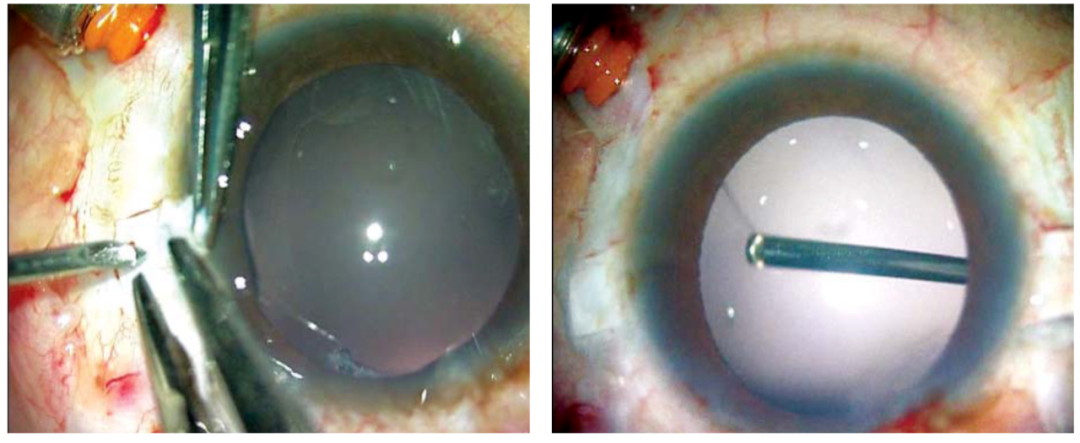

在IOL襻的理想出口处进行巩膜局部切除和电灼。插入灌注套管或前房维持器。如果使用灌注套管,可以使用23G无缝线的穿刺器和导管。灌注套管最好位于鼻下内侧象限,以防干扰巩膜瓣的制作。制作两个大约2.5mm×3 mm的巩膜瓣,对角相距180度(图 1A 和 B)。然后通过玻璃体腔或前路进行23G玻璃体切割术,以解除所有玻璃体牵拉。在巩膜瓣下,大约离角膜缘1.0mm处进行两个直的巩膜切口。然后制作一个透明的角膜/巩膜隧道切口以植入IOL。IOL植入时,术者一手使用McPherson钳,另一手使用23G/25G的夹持钳(Micro Surgical Technology, USA)通过下方巩膜切口。可以使用任何末端开口的镊子,夹住IOL襻的尖端,沿着襻的曲线穿过下方的巩膜切口并将其拉出(图2A和B),使其在下方巩膜瓣下露出。同样,通过巩膜瓣下的上方巩膜切口,也可以将襻的尾端露出。如果制作的是巩膜隧道切口,用10-0单丝尼龙线缝合切口。然后将襻的尖端塞入用26G针制作的巩膜隧道的延伸点中。用纤维蛋白胶闭合巩膜瓣(图3A和图B)。移除前房维持器或灌注套管。结膜也用相同的纤维蛋白胶闭合(图4)。

图1A和B:距离角膜缘1.5mm处制作约2.5*3mm的巩膜瓣。两个瓣成180°对角相对。